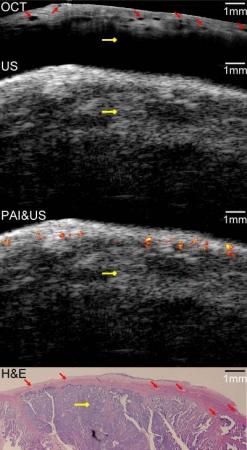

现在,使用这种全新的混合成像技术将能有效的进行卵巢癌的早期诊断。通过使用这台机器,科学家们能通过结合光声成像的对照照片、光学连续X线断层摄影术成像的高清表面照片、以及脉冲回波超声成像的组织深度成像照片来对卵巢癌进行诊断。他们在最新一期的《Biomedical Optics Express》杂志中详细描述了测试方法和结果。

Ovarian cancer has the lowest survival rate of the gynecologic cancers because it is predominantly diagnosed in Stages III or IV due to the lack of reliable symptoms, as well as the lack of efficacious screening techniques. Detection before the malignancy spreads or at the early stage would greatly improve the survival and benefit patient health. In this report, we present an integrated optical coherence tomography (OCT), ultrasound (US) and photoacoustic imaging (PAI) prototype endoscopy system for ovarian tissue characterization. The overall diameter of the prototype endoscope is 5 mm which is suitable for insertion through a standard 5-12.5mm endoscopic laparoscopic port during minimally invasive surgery. It consists of a ball-lensed OCT sample arm probe, a multimode fiber having the output end polished at 45 degree angle so as to deliver the light perpendicularly for PAI, and a high frequency ultrasound transducer with 35MHz center frequency. System characterizations of OCT, US and PAI are presented. In addition, results obtained from ex vivo porcine and human ovarian tissues are presented. The optical absorption contrast provided by PAI, the high resolution subsurface morphology provided by OCT, and the deeper tissue structure imaged by US demonstrate the synergy of the combined endoscopy and the superior performance of this hybrid device over each modality alone in ovarian tissue characterization.